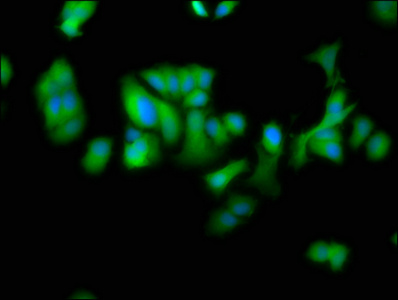

Immunofluorescence staining of MCF-7 cells with CSB-PA822207LA01HU at 1:100, counter-stained with DAPI. The cells were fixed in 4% formaldehyde, permeabilized using 0.2% Triton X-100 and blocked in 10% normal Goat Serum. The cells were then incubated with the antibody overnight at 4°C. The secondary antibody was Alexa Fluor 488-congugated AffiniPure Goat Anti-Rabbit IgG(H+L).